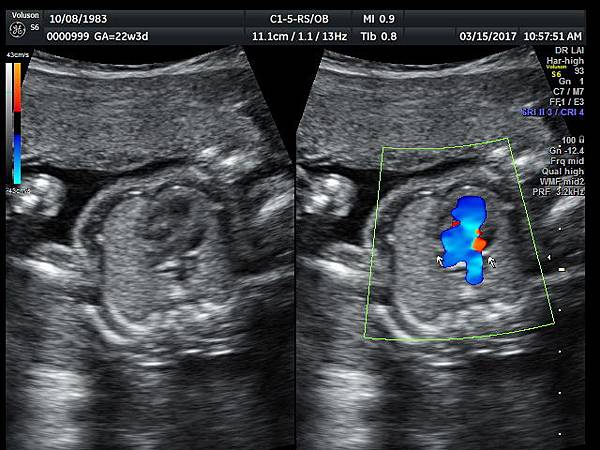

2017年3月15日33歲第一胎試管嬰兒懷孕22週3天的孕婦 、在我的診所接受胎兒心臟及高層次超音波檢查,檢查結果是單純持續性左側上腔靜脈(PLSVC),沒有合併其他異常(附圖 1~3),孕婦之前已經接受24000元的非侵入性染色體基因篩檢(NIPS),沒有異常發現,我的建議是追蹤檢查即可,如果真的很不放心,也可以考慮抽羊水做染色體及基因晶片檢查(array - CGH)。

39 22 weeks isolated PLSVC -2

38 22 weeks isolated PLSVC -1